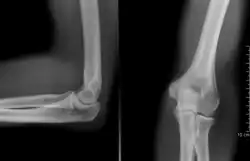

Nos ossos, a radiografia acusa fraturas, tumores, distúrbios de crescimento e postura. Nos pulmões, pode proporcionar o diagnóstico da pneumonia ao câncer. Em casos de ferimento com armas de fogo, ela é capaz de localizar onde foi parar o projétil dentro do corpo. Para os dentistas, é um recurso fundamental para apontar as cáries. Na densitometria óssea, os raios X detectam a falta de mineral nos ossos e podem acusar a osteoporose, comum em mulheres após a menopausa. Na radiografia contrastada, é possível diferenciar tecidos com características bem similares, tais como os músculos e os vasos sangüíneos, através do uso de substâncias de elevado número atômico (iodo ou o suspensão de sulfato de bário). Ainda, o raio-X possibilitou o surgimento de exames como a tomografia axial computorizada (TAC) que, com ajuda do computador, é capaz de fornecer imagens em vários planos, de forma rápida e precisa, utilizando quantidades mínimas de radiação.